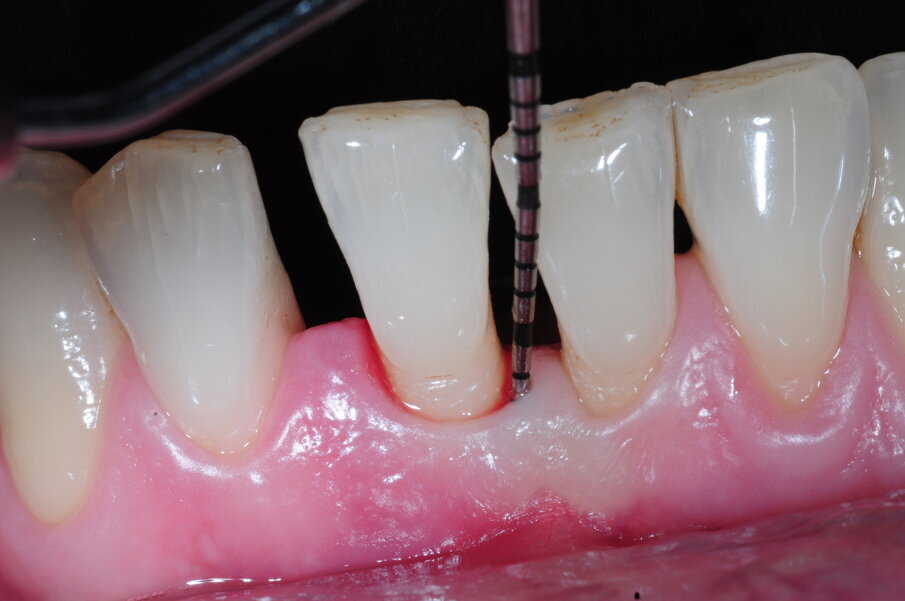

Il Paziente è stato intercettato in visita con diagnosi di parodontite cronica generalizzata da moderata a severa a seconda dei siti. È stata eseguita la terapia non chirurgica in regime di Full mouth disinfection in unica seduta seguita da controlli settimanali fino al raggiungimento della guarigione a 2 mesi dalla strumentazione. In tale fase sulla base della valutazione dei siti con PD>5 mm e dell’anatomia dei difetti infra-ossei o sovra ossei presenti viene normalmente discussa con il paziente la fase di chirurgia correttiva, se necessaria. Nel Paziente in questo caso residuava a livello di 41 un difetto infra-osseo (Figg. 6a-6c).

Figg. 6a, 6b - Sondaggio iniziale del difetto.